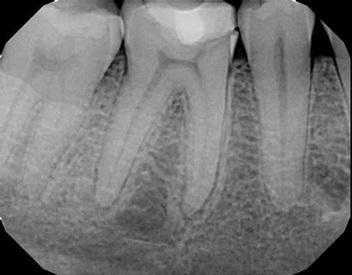

Данные, полученные врачом после сбора анамнеза, рентгенологического обследования и клинического осмотра, как правило, позволяют с достаточно большой точностью идентифицировать проблемный зуб и приступить к его лечению. Пациенты в процессе сбора анамнеза зачастую сообщают о наличие болевых ощущений на термальные раздражители, во время жевания, развитие внутриротового и внеротового отека и формирование свища. В ходе клинического осмотра стоматолог проверяет чувствительность пульпы и реактивность тканей периодонта таким образом, чтобы спровоцировать развитие определенных симптомов. Диагностика состояния пульпы предполагает провокационное действие холодовых факторов и проведение электроодонтодиагностики, а диагностика состояния периодонта - проведение перкуссии, оценку реакции на накусывание и пальпацию. Зачастую пациенты с пульпитом, некрозом пульпы, периодонтитом или апикальным абсцессом характеризуются наличием типичных симптомов, которые относительно просто дифференцировать. Проблемные зубы, как правило, достаточно выражено реагируют на холод, тепло и давление. Для подтверждения клинических предположений можно дополнительно провести прицельную рентгенографию. Стандартными для эндодонтического лечения являются рентгенограммы, полученные по методике bite-wing и периапикальной техникой. Конечно же, снимки, полученные данными методиками, характеризуются определенным уровнем дисторции и взаимоперекрытием контура одних структур другими. Новые технологии по типу конусно-лучевой компьютерной томографии (КЛКТ) обеспечивает лучшую диагностическую точность и характеризуются большим диапазоном возможностей для верификации эндодонтических поражений.

Фото 2. Клинический случай 1. Рентгенограмма области дистального правого квадранта верхней челюсти без выраженных признаков изменений.

Фото 3. Клинический случай 1. Рентгенограмма области дистального правого квадранта нижней челюсти без выраженных признаков изменений. Наличие ретинированного моляра.

Фото 5. Клинический случай 2. Рентгенограмма области дистального правого квадранта верхней челюсти.

Фото 6. Клинический случай 2. Рентгенограмма области дистального правого квадранта нижней челюсти.